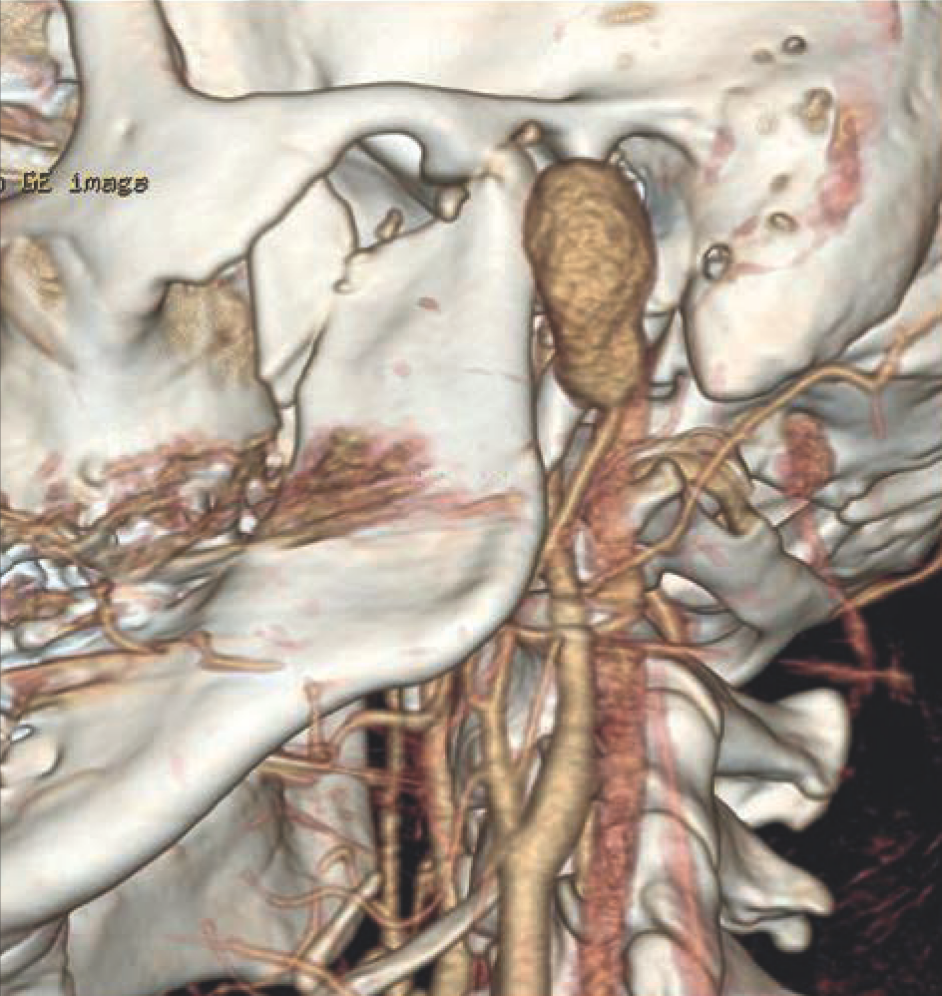

Przy przyjęciu stan ogólny chorego był dobry. Klinicznie widoczna była asymetria twarzy spowodowana obrzękiem okolicy przedusznej po stronie lewej. Rana powłok skórnych o długości około 2 cm zaopatrzona szwami. Poza tym powłoki skórne były niezmienione, bez cech stanu zapalnego. Przy palpacji wyczuwalne było wzmożone napięcie tej okolicy i tętnienie. Poza tym w badaniu klinicznym bez odchyleń od normy. Ze względu na wywiad, badanie kliniczne oraz brak możliwości obrazowania tętniaka w rutynowym badaniu TK wykonano badanie ultrasonograficzne, a następnie angiografię tomografii komputerowej, która uwidoczniła obecność tętniaka rzekomego o wymiarach 31 x 20 x 21 mm zlokalizowanego na poziomie odejścia tętnicy szczękowej od tętnicy szyjnej zewnętrznej lewej (ryc. 2).

Ryc. 2. Angiografia tomografii komputerowej – widoczny tętniak rzekomy, złamanie wyrostka kłykciowego i dziobiastego żuchwy po stronie lewej.